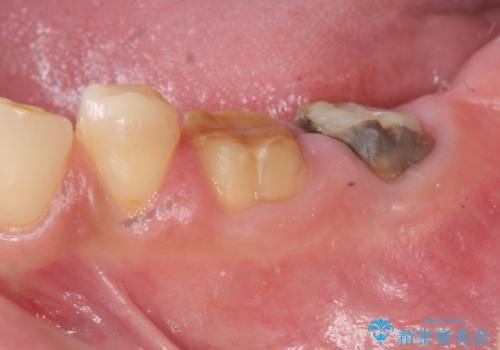

- 著しい歯ぎしりですり減ってしまった、奥歯のクラウンのやりかえを希望され来院されました。

このままの状態でクラウンのやりかえを行うと高さが低く安定の悪いクラウンとなってしまうため、事前に歯周外科手術を行い歯ぐきを下げることで安定性の高いクラウンを製作する治療計画としました。